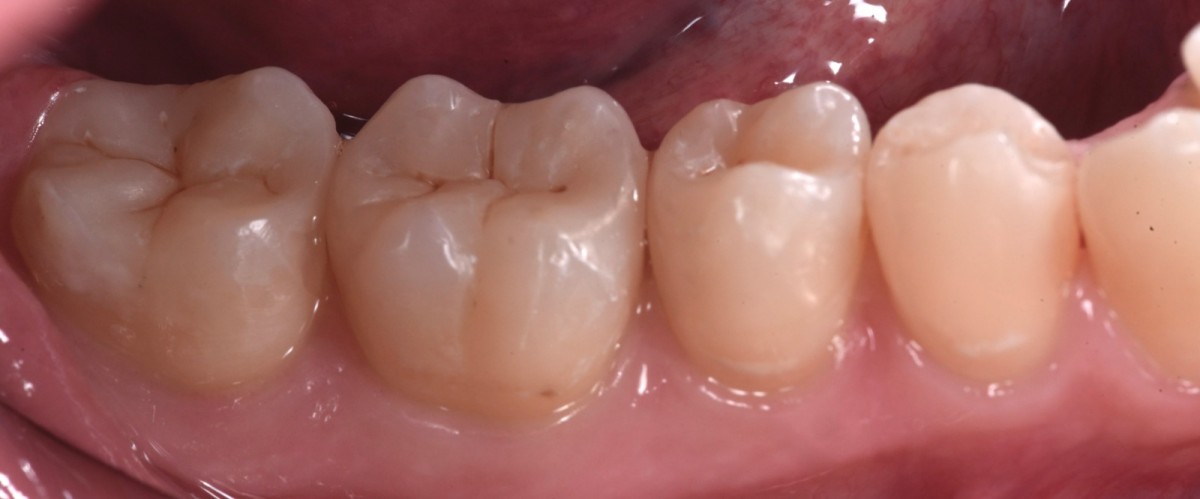

Immediately after rubber dam removal (Fig.13).

6-months follow up (after finishing and polishing) (Fig.14).

Detail of the vestibular part, showing good health of periodontal tissues. 3.8 element will be extracted as soon as possible to avoid probing distal to 3.7 (Fig.15).

Final rx bitewings (Fig.16).